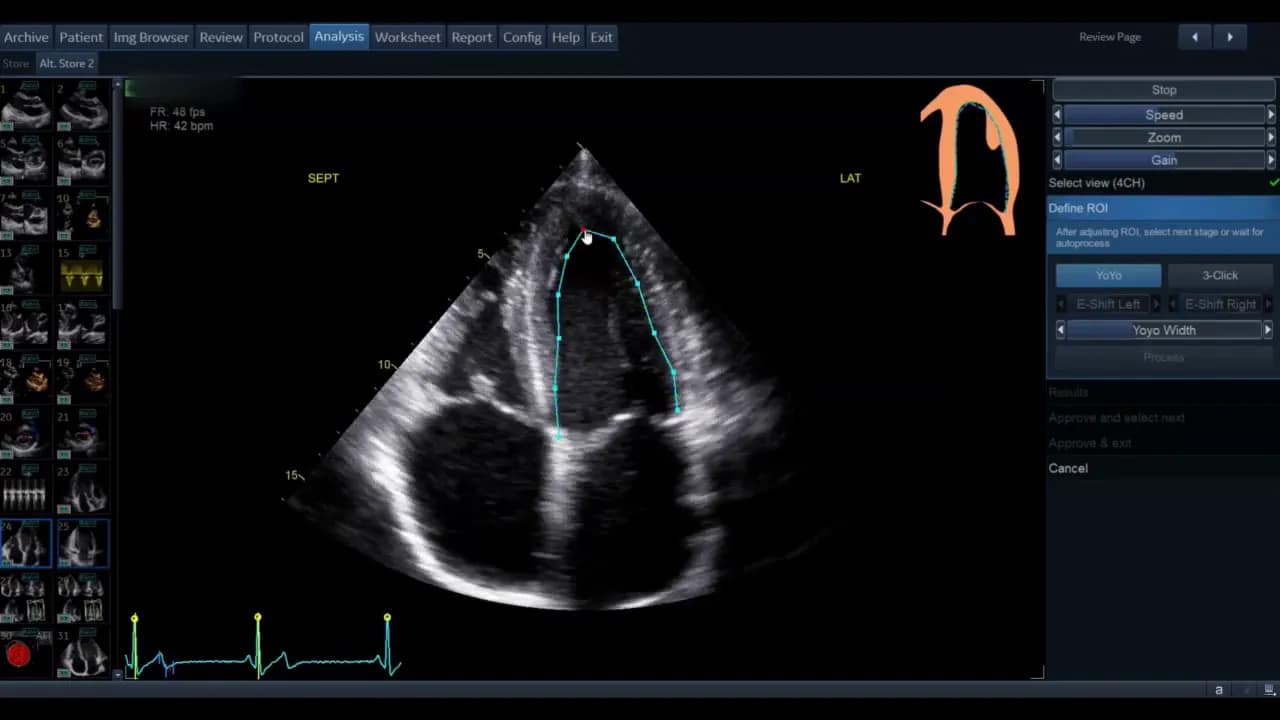

Sobald die Ansicht gewählt ist, gelangen Sie in die Phase der ROI‑Definition. Hier legt die Software die initiale Kontur für die automatische Wandsegmentverfolgung fest.

Die Standardkontur wird als grüne Linie (modellabhängig) angezeigt. Bewegen Sie den Cursor über diese Linie; rote Kreise erscheinen als Griffpunkte, die Sie anklicken, verschieben und loslassen können. Ziel ist eine möglichst genaue Platzierung entlang des inneren Myokardrandes ohne Papillarmuskeln und Trabekel zu ignorieren, soweit die Software dies zulässt.

- Wenn die vorgegebene Kontur passend ist, genügt das geringe Feintuning.

- Wenn die Kontur unbrauchbar erscheint, nutzen Sie die Drei‑Punkt‑Option. Dabei markieren Sie basal‑septal, basal‑lateral und den Apex manuell. Die Software interpoliert zwischen den Punkten.

Nach der manuellen Markierung können Sie die so erzeugte grüne Kontur wiederum per Griffpunkte feinjustieren. Ziel ist, dass die Kontur den endokardialen Rand im gesamten Zyklus plausibel abdeckt.